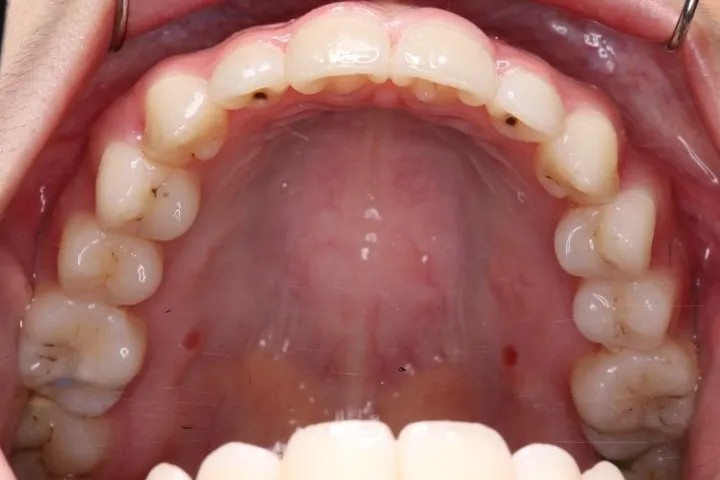

• 初診

初診時年齢 高校生 (女性) 主訴 歯並びがガタガタ・口元の突出感

診断名 叢生・開咬・上下顎前突 装置名

特徴 ゆがんで生えている

状態 ガタガタ・でこぼこに生えている(叢生)

受け口(下顎前突/反対咬合)

前歯で噛めない(開咬/オープンバイト)

上下前歯、口元が出ている、口ゴボ(上下顎前突)

ガタガタの歯並びにお悩みの患者様でした。

口唇の突出感の他、下顎面高が長い印象も認められました。